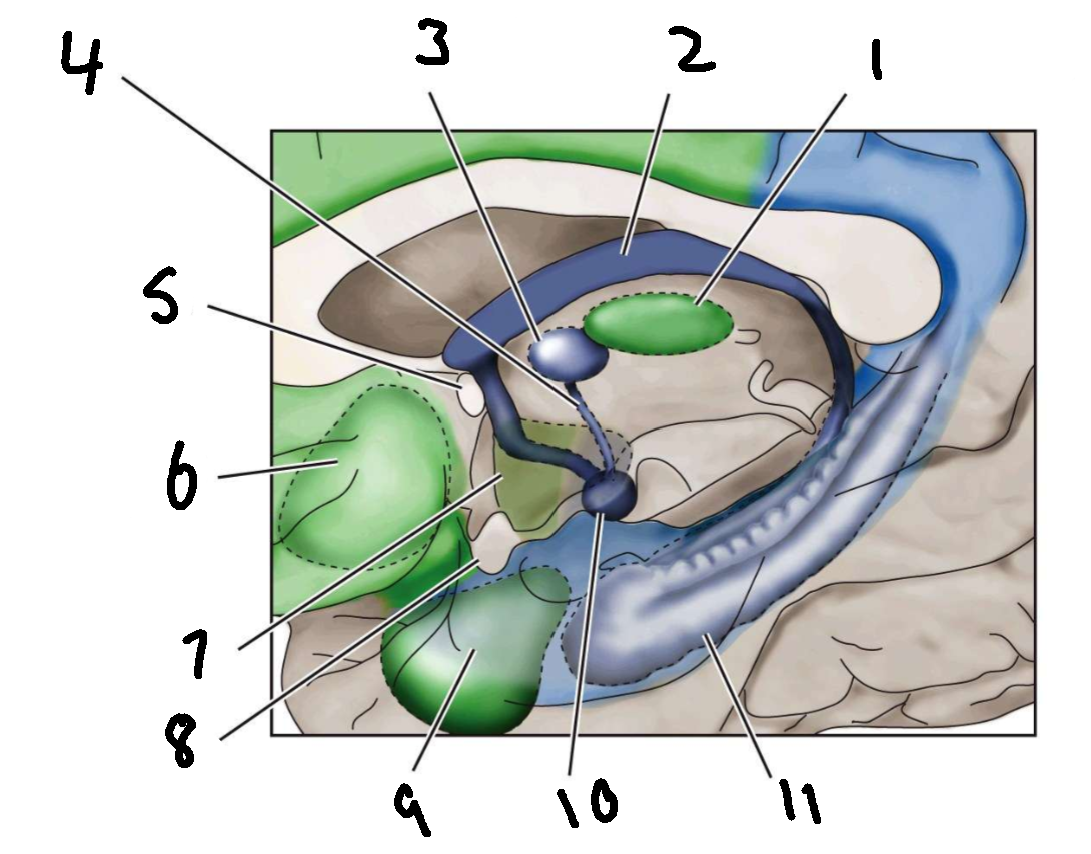

What is 1?

mediodorsal nucleus of the thalamus

What is 2?

fornix

What is 3?

anterior nucleus of the thalamus

What is 4?

mammillothalamic tract

What is 5?

anterior commissure

What is 6?

ventral basal ganglia

What is 7?

hypothalamus

What is 8?

optic chiasm

What is 9?

amygdala

What is 10?

mammillary body

What is 11?

hippocampus